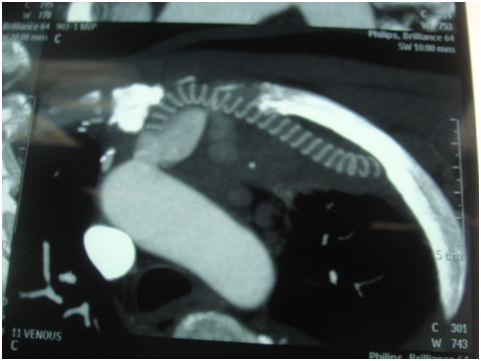

A 55 years old gentleman came to our hospital with discharging chest wound with occasional bleeding through upper chest wound. He was also suffering from fever occasionally. One and half years back he was operated in another hospital with CABG with Aorto-axillary bypass. On 4th postoperative day he needs reopening for mediastinal bleeding and needed a long ICU stay. Then he developed above mentioned symptoms. 5 days back he developed severe bleeding and was treated conservatively in another hospital. After admission CT angiogram was done-showed-Aorto-axillary bypass graft penetrating sternum and developed a leak in the aortic side. We decided for urgent operation on next day on 1.08.13-we went to femoro-femoral bypass first [1].

Figure 1: Aorto-axillary bypass-leak in aneurysmal aortic end.

Figure 2: Aorto-axillary bypass-showing leak and eroding sternum.